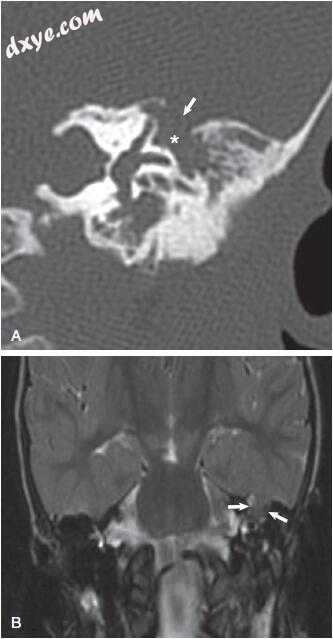

图-1. 颞骨骨扫描计算机断层扫描显示乳突的浑浊与保留骨隔。 注意皮质骨(白色箭头)和耳后肿胀和液体收集(黑色箭头)的缺陷。

图-2. 轴向(A)和冠状(B)颞骨计算机断层扫描显示乳突浑浊,伴有骨隔缺失。 注意皮质骨和耳后液采集中的缺陷(箭头)。